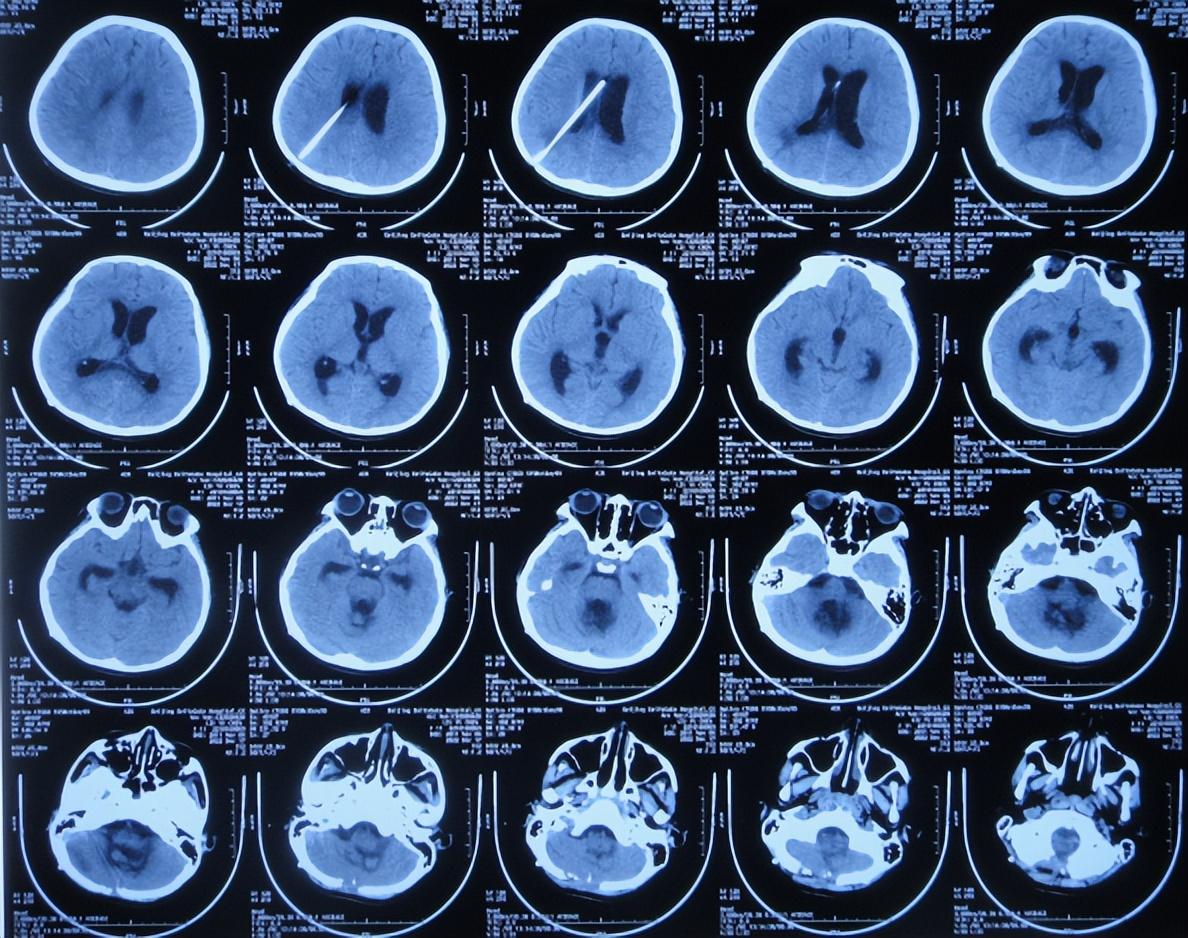

脑ct片子 头颅

头部ct示排除颅内出血

收藏!超详细的头部ct读片详解

ct入门颅脑ct精美解剖详细标注

详细颅脑ct正常解剖图谱,带标注,值得收藏!

收藏超详细的头部ct读片详解